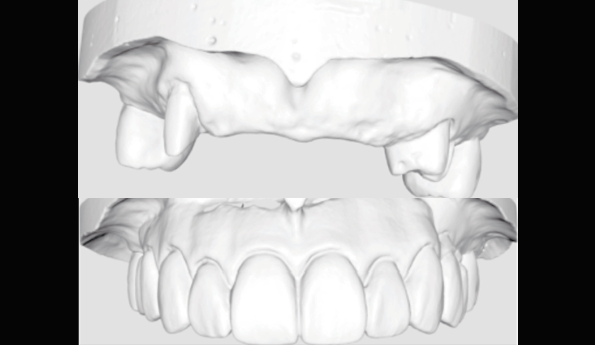

Fig 8. Full-contour waxing was made according to teeth proportion and position.

Fig 9. Prepared cast and Diagnostic cast were scanned and transformed into STL file.

Aesthetic analysis was performed with evaluation of the smile line, incisal profile, length and proportion. Diagnostic wax-up was fabricated according to the aesthetic evaluation. (Fig. 8)

Provisional full arch bridge fabrication (Fig. 8 - 19)

Preparation cast with a diagnostic wax-up ca st was sent to a local laboratory for scanning and transforming into STL (Stereolithography) digital impression file. (Fig 8,9.) Two sets of STL impressions were super-imposed in the software in order to subtract the overlapping data. This process was done in order to transform the diagnostic wax-up into the STL digital impression. Consequently, the STL data was sent to the laboratory for milling. (Fig10.) A monochromatic milled-PMMA temporary bridge was fabricated in a local laboratory and returned to the dentist for composite layering. (Fig 11.) Gingival cutback was made to create sufficient gingival space for pink composite layering (Fig 12). Prior to composite layering CeraResin Bond 1 was applied and left for 10 seconds to prime the surface, followed by application of CeraResin Bond 2 for 10 seconds and light cured for 20 seconds (Fig 13.). Ceramage Indirect Composite gingival shade GUM-O (GUM Opaque) was applied to mask the color of PMMA (Fig 14.). GUM-D (GUM Dark) was applied on the attached gingiva area to the buccal flange (Fig 15.). GUM-L (GUM Light) was applied in the region of free gingiva (Fig 16.). F-GUM-R (Flowable GUM Red) and F-W (Flowable GUM White) were painted to mimic the mucogingival junction and vascular alveolar mucosa (Fig 17.) GUM-T (GUM Translucent) was applied to reproduce of reddish translucent gingiva areas (Fig 18) to achieve natural gingival aesthetics.